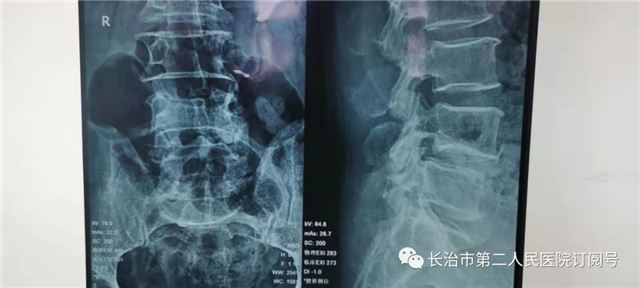

患者李某,男性,70岁,主因“腰及左下肢困痛不适5年多”。连日来的病情不断加重,腰部及左下肢疼痛难忍,入住我院,腰椎X线片检查显示:腰4/5椎体后缘自然弧线不连续呈滑脱征象,结合体格检查和影像学检查,诊断为:腰椎滑脱症、腰椎间盘突出。

术前影像